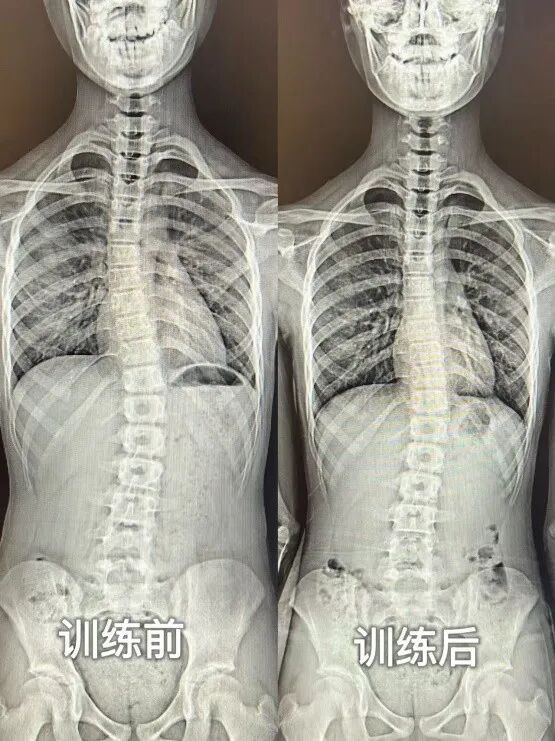

脊柱侧弯是脊柱的三维畸形,于冠状面、水平面、矢状面呈现异常弯曲与旋转,X 光 下 Cobb 角>10° 即可确诊。其病因繁杂,涵盖先天性、特发性、神经肌肉性、功能性等,其中特发性最为常见,约占 80%,且女性多发。